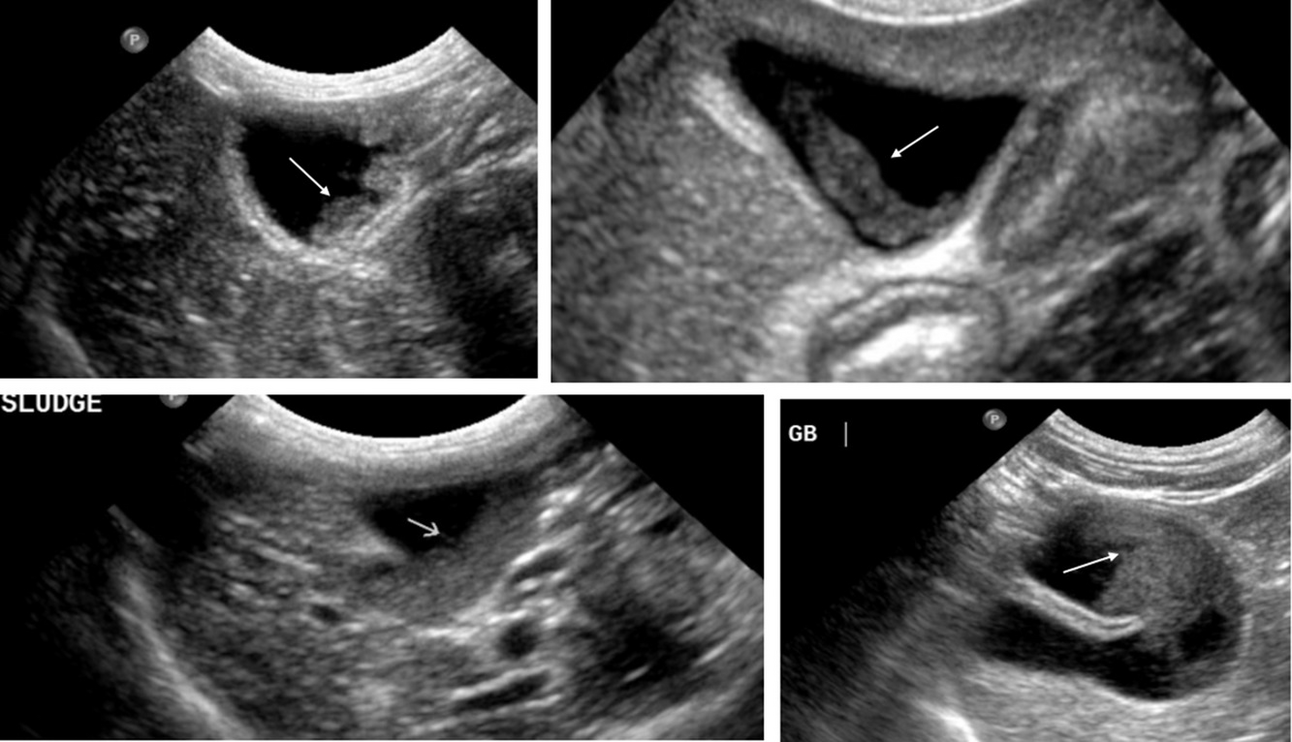

Feline abdominal ultrasonography what’s normal? what’s abnormal? The Can Cats Live Without A Gallbladder Infectious diseases of the liver several types of infections may cause liver disease, including viral, bacterial, fungal, and parasitic disease. The surgery can be performed by a veterinary. Here’s what i told a reader who contacted. if successful, your cat can live without its gallbladder successfully, and surgery to remove the gallbladder itself or any. dogs and cats. Can Cats Live Without A Gallbladder.

Gallbladder Sludge in Cats Prevalence and Clinical Significance Can Cats Live Without A Gallbladder The surgery can be performed by a veterinary. your cat can live without its gallbladder successfully, and surgery to remove the gallbladder will resolve the condition. obviously you can survive without a gallbladder, but you are more prone to developing certain health problems. cats with acquired shunts can live several years without any signs, and some can. Can Cats Live Without A Gallbladder.